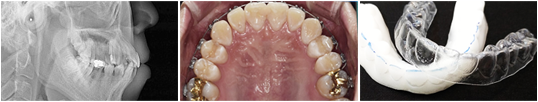

디지털 치아교정

얼굴 모습의 조화와 아름다운 미소까지 선사하는 교정

백년치과의 치아교정은 디지털 교정으로

보다 가지런하고

바른교정이 진행되고 있습니다.

치아교정은 교정상담에서 사후관리까지 책임지고 관리하여 만족도가 높습니다.

수준 높은 의료진은 개개인에 특화된 치료계획과 환자를 책임지는 사명감으로 10년, 20년 후에도

반듯함을 유지하는 치아교정의 효과를 얻으실 수 있습니다.

전문의 교정진단